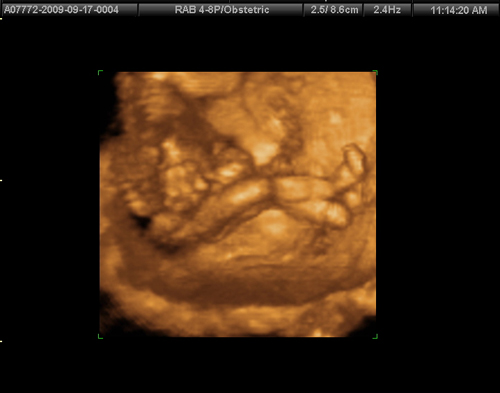

Babócánk már 12 cm!!!

Babócánk már 12 cm!!!

Babócánk már 137 gramm!!!

Babócánk már 137 gramm!!!

Babócánk lábacskái!!!

Babócánk lábacskái!!!